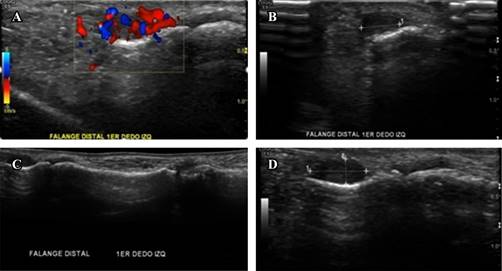

La ecografía reportó lesión nodular altamente vascularizada sin sombra ni refuerzo posterior, circunscrita, hipoecoica y homogénea de 3.00 × 2.10 mm en borde medial de falange distal del primer dedo más engrosamiento de la vaina sinovial; los cuales son hallazgos característicos del tumor glómico (Figura 2).7

Figura 2: A) Ultrasonido Doppler con reporte de lesión nodular altamente vascularizada en borde medial de falange distal del primer dedo de origen a determinar. B-D) Lesión nodular de 3.00 × 2.10 mm en borde medial de falange distal del primer dedo más engrosamiento de la vaina sinovial.

Takanashi y asociados,12 en su estudio retrospectivo de 18 pacientes quienes fueron diagnosticados histopatológicamente con tumores glómicos después de la realización del estudio ultrasonográfico, revelaron que la mayoría de los tumores contenían márgenes definidos, abundante flujo sanguíneo y con tamaños de hasta 5 mm; señalan la importancia de este estudio como herramienta del día a día para la detección de pequeños tumores subcutáneos dolorosos, por lo que deben considerarse como la primera opción en el diagnóstico de imágenes debido a su bajo costo y por la seguridad que ofrece, ya que no emplea radiaciones; además, es muy efectiva, fácilmente reproducible y puede realizarse en cualquier hospital o en un consultorio.5,6,12,13 En nuestra paciente, la ecografía mostró una imagen nodular hipoecoica, homogénea bien delimitada y altamente vascularizada (Figura 2), la cual resulta similar en cuanto a los hallazgos reportados en la literatura11,12,14 y que fueron clave para el diagnóstico y la elección de tratamiento.11,15 Por otro lado, los exámenes hematológicos fueron normales.